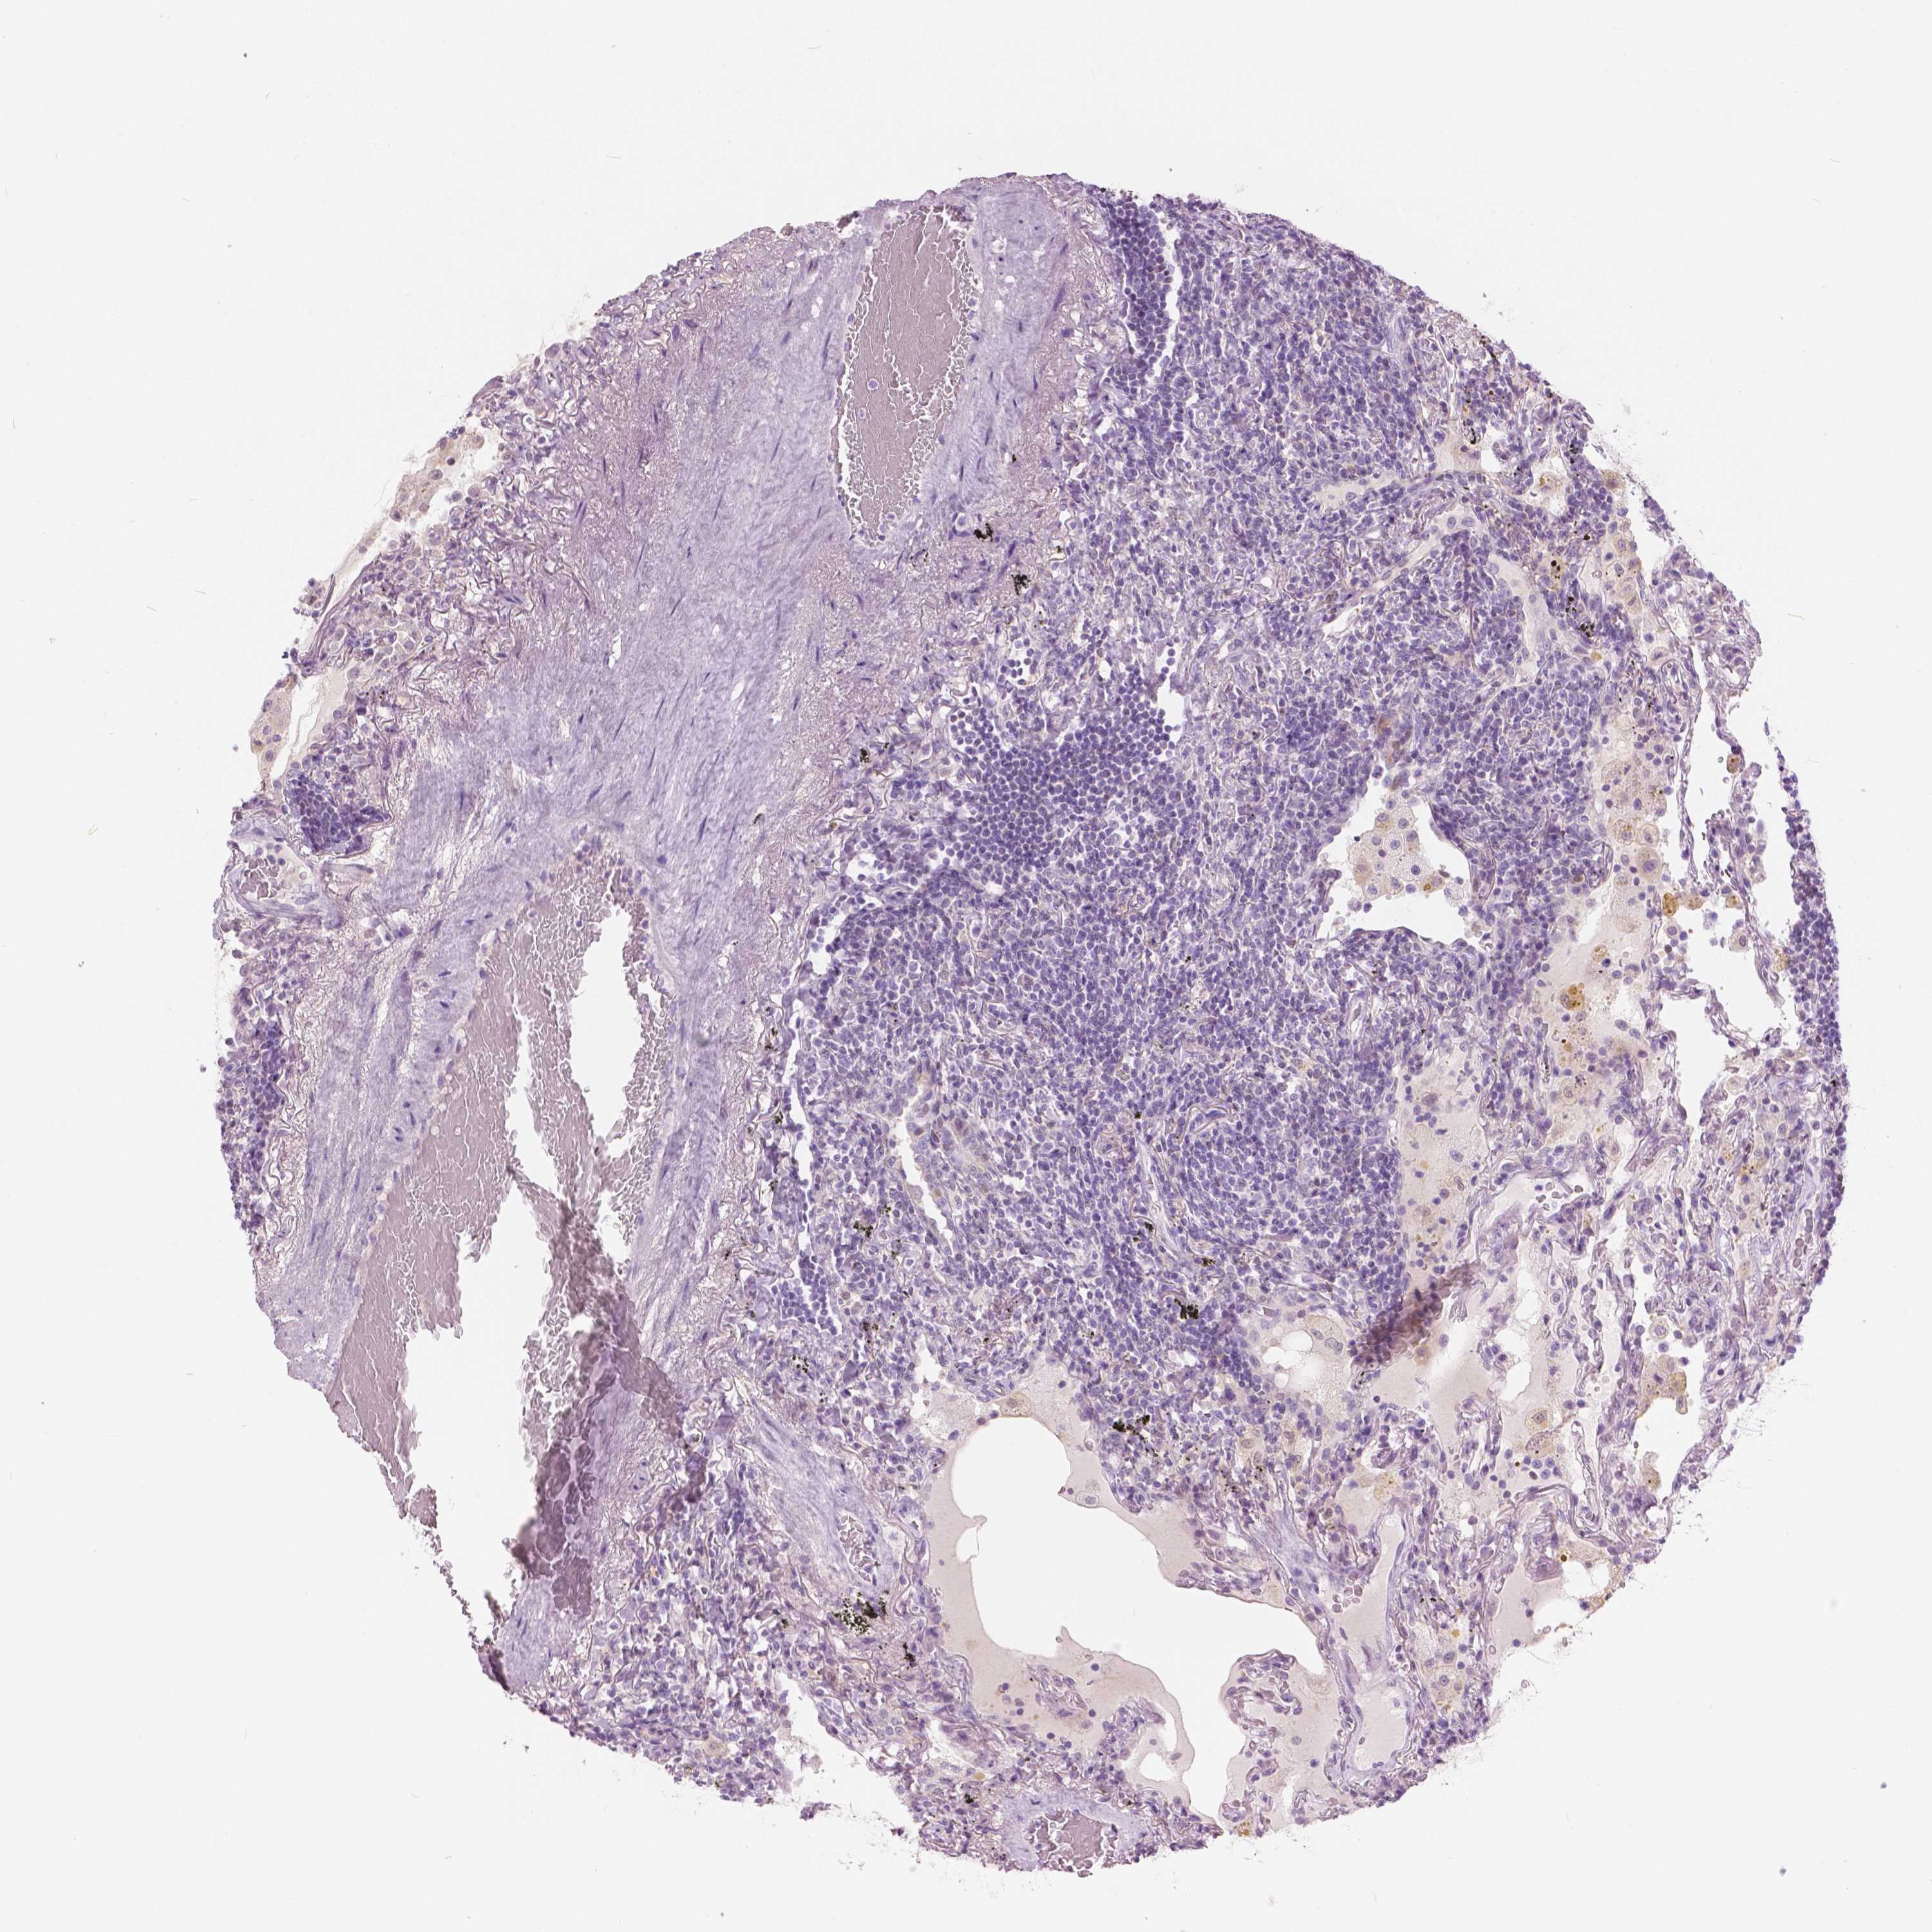

LYMPHOMA - Protein expressioni

A mouse-over function shows sample information and annotation data. Click on an image to view it in a full screen mode. Samples can be filtered based on level of antibody staining by selecting one or several of the following categories: high, medium, low and not detected. The assay and annotation is described here.

Antibody stainingi

Antibody staining in the annotated cell types in the current human tissue is reported as not detected, low, medium, or high, based on conventional immunohistochemistry profiling in selected tissues. This score is based on the combination of the staining intensity and fraction of stained cells.

Each image is clickable and will lead to virtual microscopy that enables deeper exploration of all samples and also displays staining intensity scores, fraction scores and subcellular localization as well as patient and tissue information for each sample.

Antibody HPA035472

Antibody HPA035473

Antibody HPA064835

Malignant lymphoma, non-Hodgkin's type, Low grade

Malignant lymphoma, non-Hodgkin's type, High grade

Hodgkin's disease, NOS